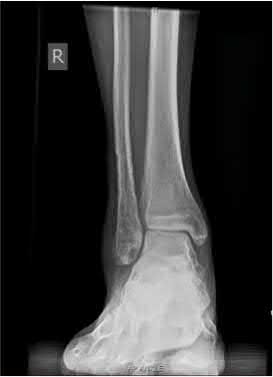

A 64-year-old woman is thrown off a horse, sustaining the injury shown in Figures A and B. She undergoes surgical fixation as seen in Figures C through E. What is the most commonly reported complication of this procedure?

The patient in the scenario has a 2-part proximal humerus fracture treated with a locking plate as seen in Figures A-E. The most common complication with the use of this implant is screw penetration. The terms screw cut out and penetration are often used interchangeably in the literature with cut out appearing more frequently in reports regarding intertrochanteric fractures.

Owsley et al retrospectively reviewed 53 proximal humerus fractures treated with locking plates and the same post-operative protocol. The most common complication was screw cut out or penetration, followed by varus displacement. They concluded that 3 and 4-part fractures in patients over 60 years have a higher incidence of failure.

Agudelo et al retrospectively reviewed 153 patients at a level-one trauma center treated with proximal humerus locking plates, investigating modes of failure for the implant. They determined that varus malreduction (head-shaft angle